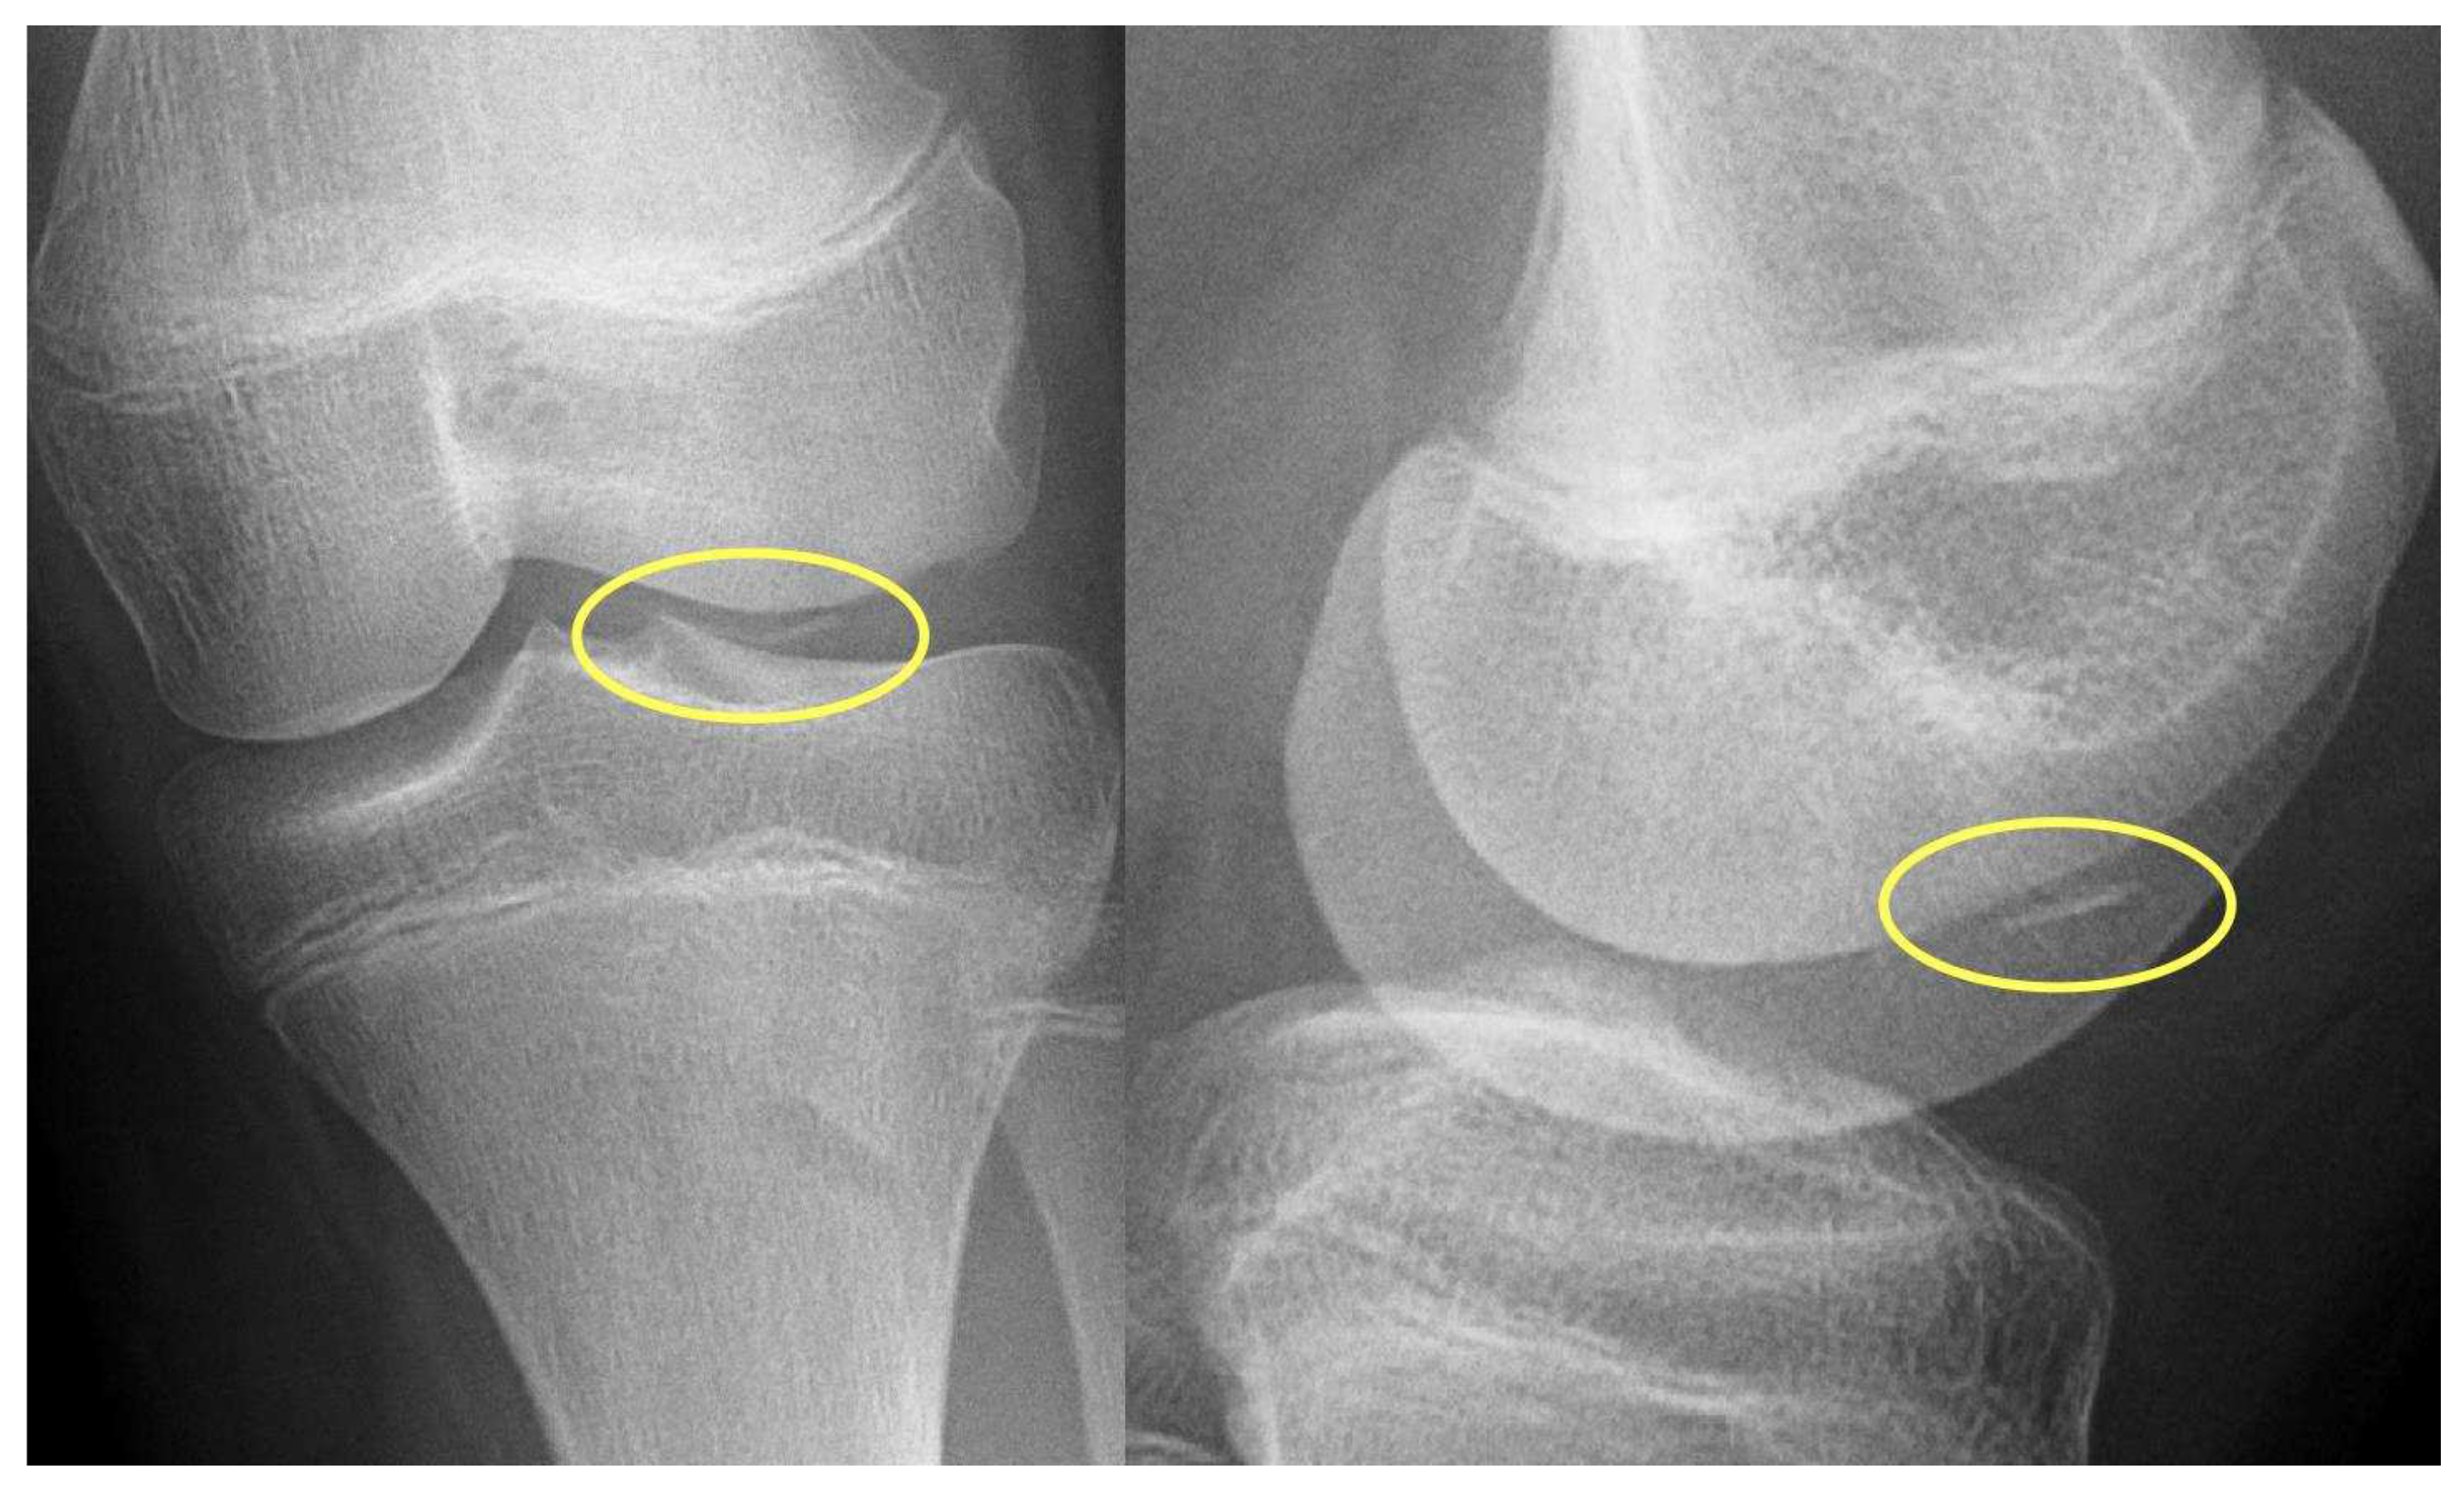

- X-ray: Lucency between fragment and normal bone.

- X-ray: Loose body, lucency